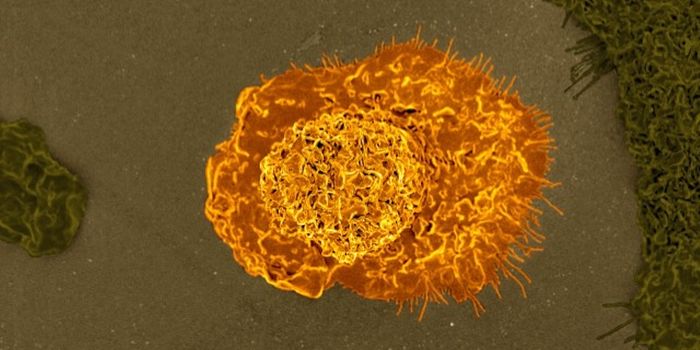

AUG 26, 2024Clinical & Molecular DXA colorized scanning electron micrograph depicts a Kupffer cell. / Credit: Thomas Deerinck, National Center for Microsco ...